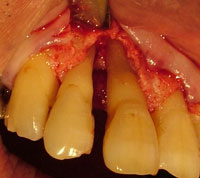

天然歯の歯周組織の骨を回復させ、隣在歯にインプラントを埋入した症例

写真にある変色歯は、歯根破折及び虫歯で歯質が感染崩壊しており、 歯周外科にて確定診断を行い、抜歯しております。

術前 エムドゲイン適応 術後